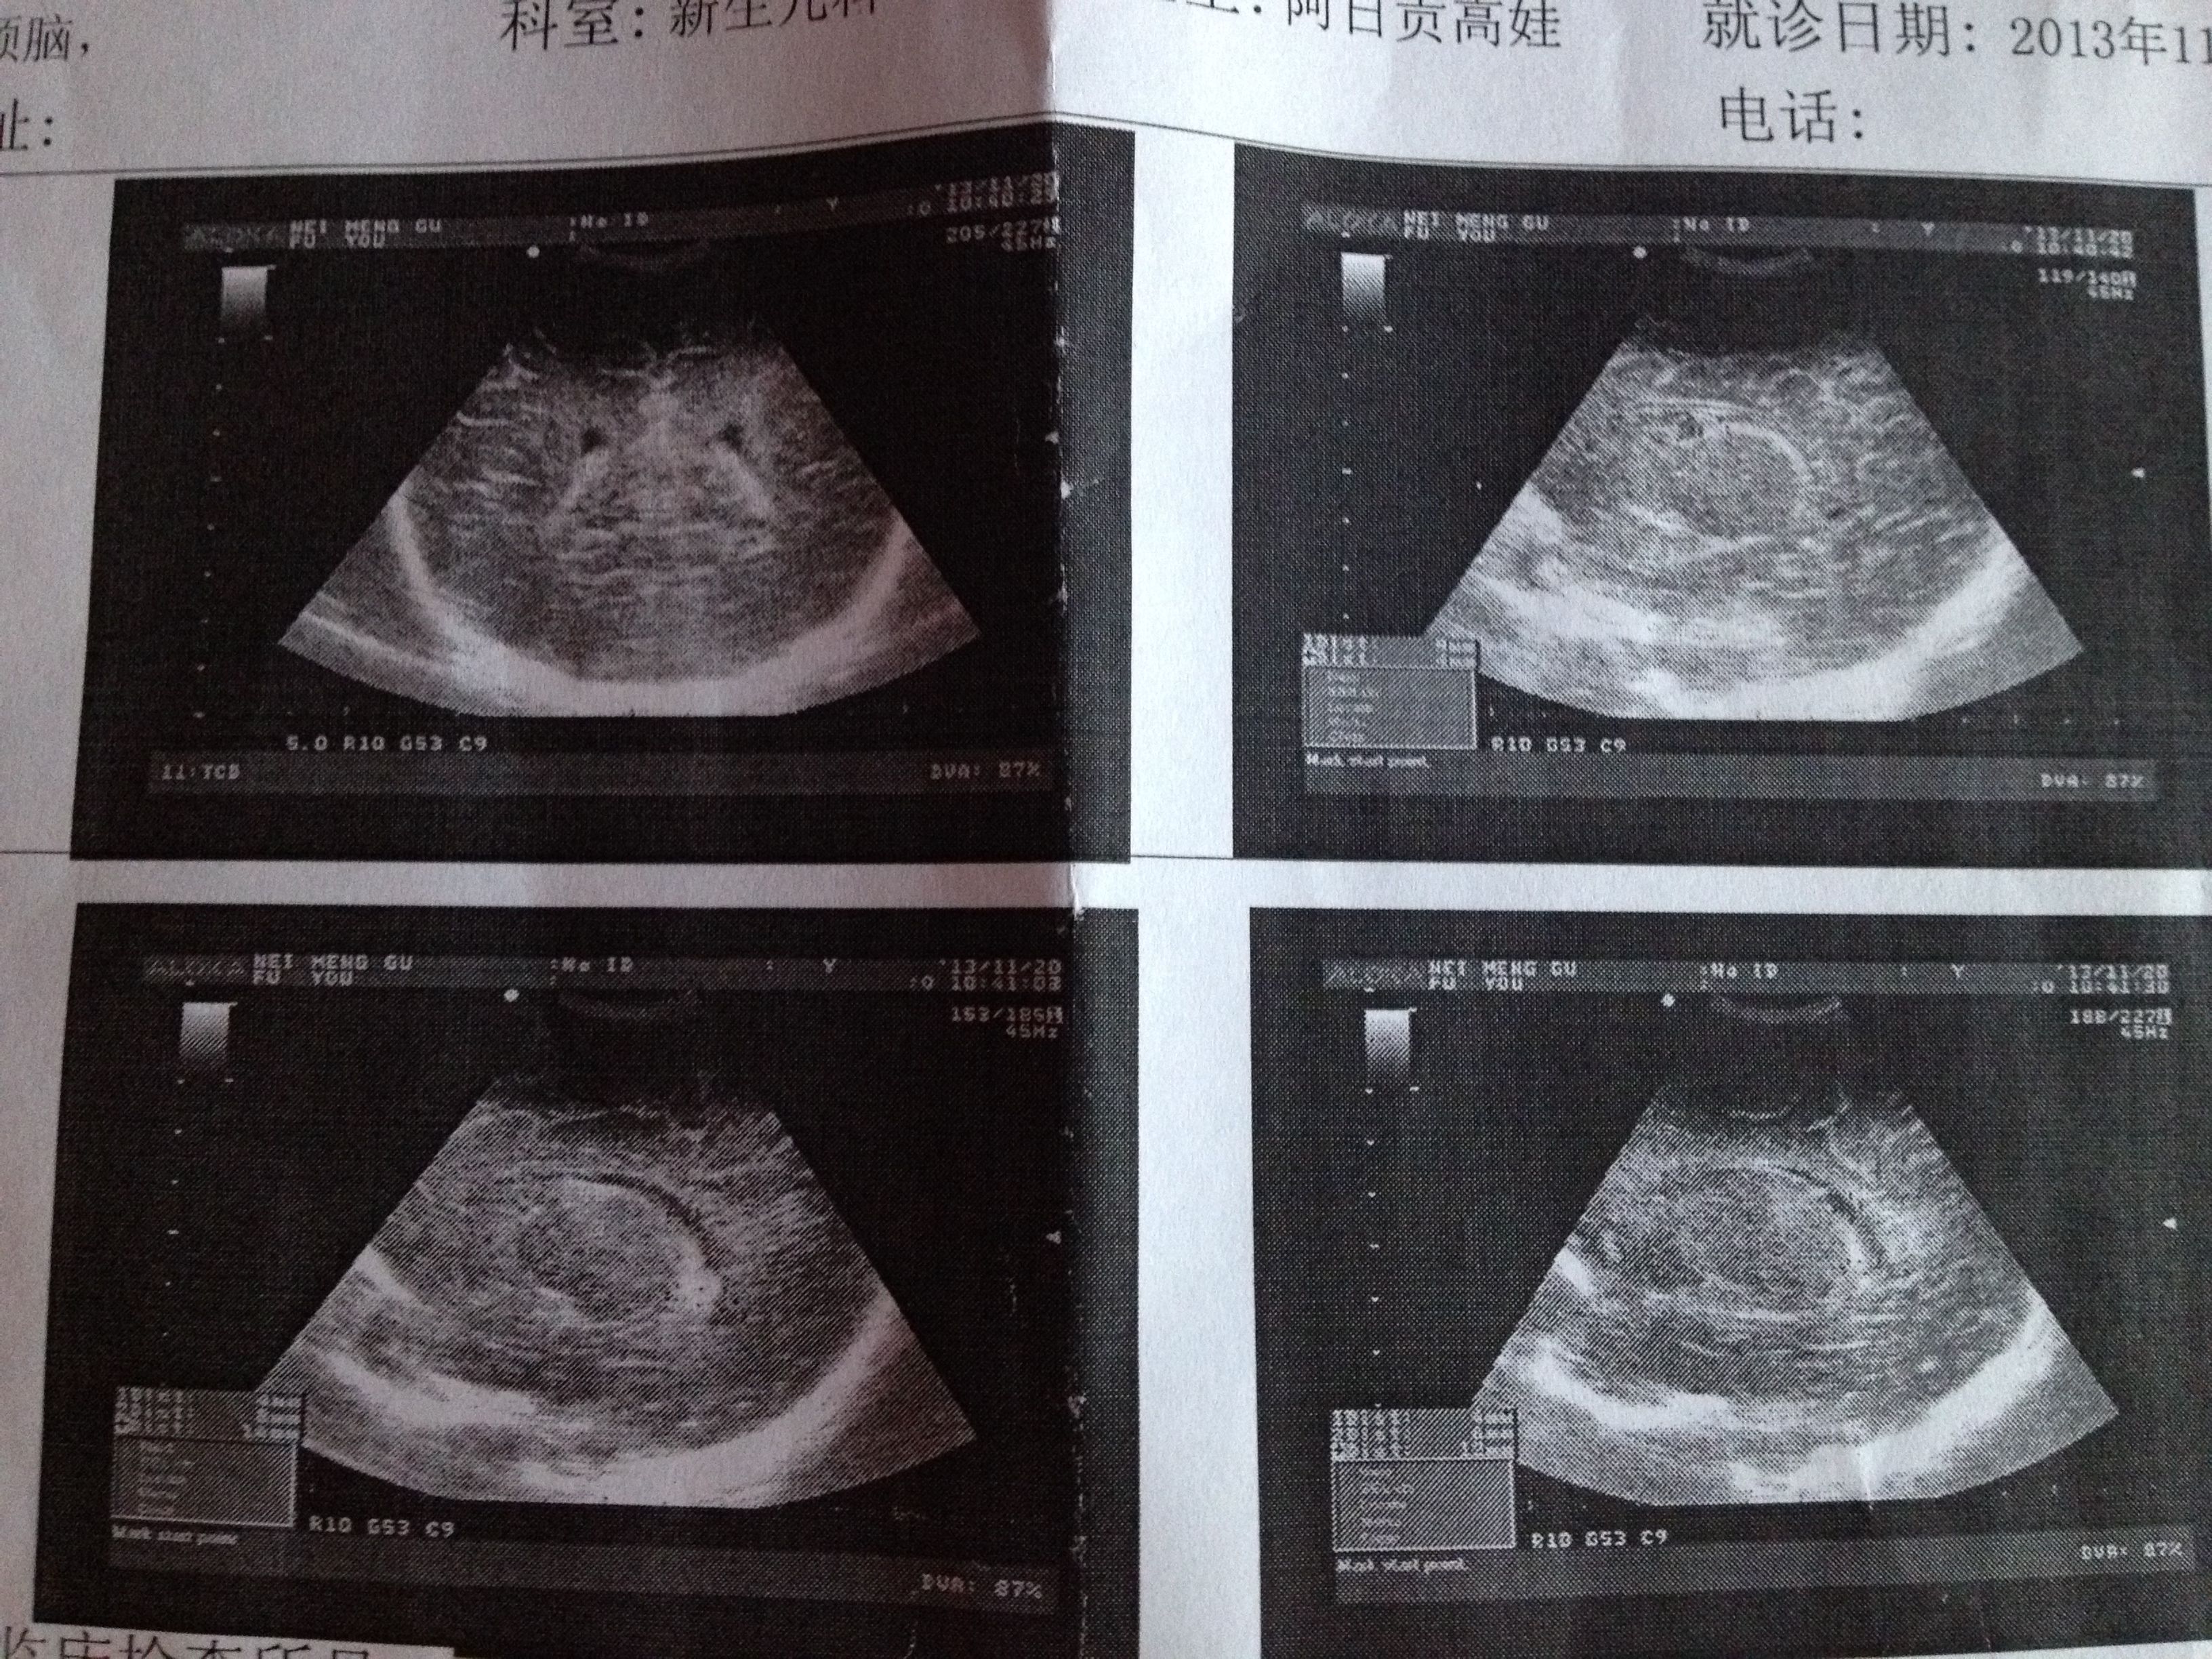

早产35+4,双侧脑室内出血二级,双侧脑室周围强回声,42天复查左侧脑室内囊腔,双侧脑室内出血三级 ,医生说不用治疗,请问需要注意什么? 点击展开 匿名用户 2013-11-22 08:56 为您推荐: 其他回答 病情分析: 您好,根据您的以上这些内容的描述,您的情况考虑是脑超的情况 指导意见: 您好,像您的这种情况考虑是进行加强检查是可以的,防止出血增加的情况 匿名用户 2013-11-22 09:08 相关问题 七个多月就生了是早产儿,现在一个月,今天去医院复查上面写的是‘双侧脑室后角增宽并脑室内出血,是怎么 脑室内出血,可不可以吃猪蹄 脑室内出血,可不可以吃老母鸡